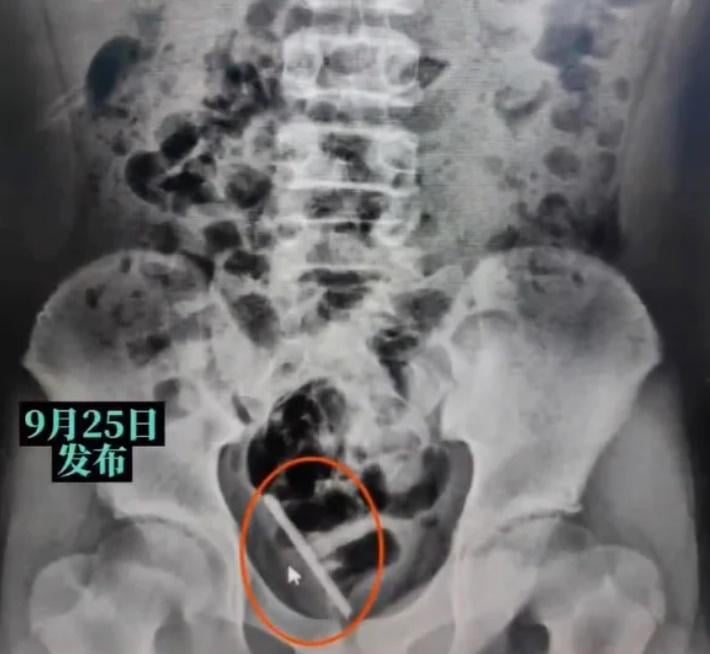

綜合報道,涉事10歲小童輝輝(化名)周日(24日)因為一時好奇,將一支接觸式探熱針插入尿道內,沒想到在過程中不慎將探熱針折斷,導致一半探熱針殘留在體內。輝輝想要自行取出,卻令探熱針愈滑愈深,並導致尿道口出血、血尿及疼痛等症狀,隨即被家人送往江西省兒童醫院求醫。經過醫院檢查後,發現折斷的探熱針殘餘部分已進入膀胱內,網上影片顯示,醫生立即為男童進行手術,將整支6.5厘米長的殘餘探熱針完整取出。目前,輝輝正在康覆中。